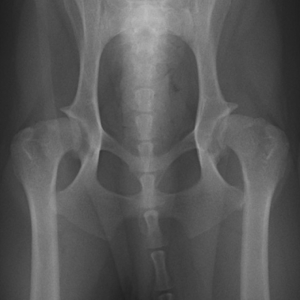

股関節形成不全

- 成長期の犬に発症する股関節の亜脱臼( しっかりと噛みあっていなくかなり緩い関節の状態 )あるいは 完全脱臼を特徴とする疾患。

- 軽度から重度の関節炎が発症する。

股関節形成不全に起因する関節炎のレントゲン像

①寛骨臼(骨盤側の関節の受け皿)

②大腿骨頭(太ももの骨の関節の頭)

③大腿骨頚(太ももの骨の関節の首)

の重度の変形